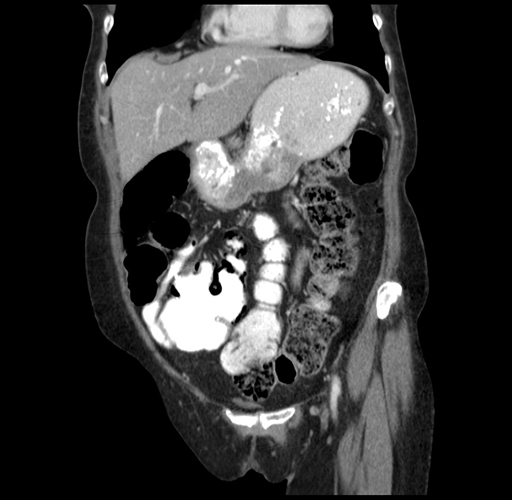

Pre-Chemo: Coronal Venous